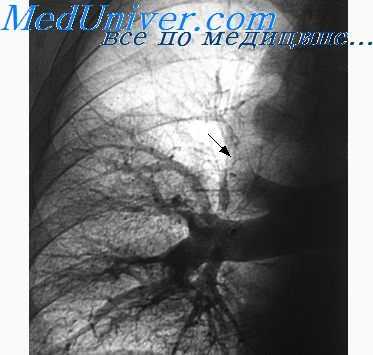

2. Выявление неоперабельных форм рака легкого вследствие прорастания магистральных сосудов в средостении. К числу ангиографических признаков неоперабельности больных раком легкого относятся сужение, дефект наполнения или полная обструкция верхней полой вены; сужение, деформация или ампутация легочной артерии в ее медиастинальном отрезке; одновременное сужение обеих долевых ветвей; дефект наполнения в предсердии; длительный стаз контрастного вещества в легочных венах (Slesser, Britt, Freer, 1954; Stiller, 1954; A. H. Новиков, А. X. Tpax-тенберг, С. Я. Марморштейн, 1964, и др.).

При шаровидных образованиях для доброкачественных опухолей и туберкулом характерно раздвигание сосудистых ветвей, тогда как при раке чаще наблюдается ампутация сегментарной или субсегментарной ветви легочной артерии, но этот признак также не является абсолютным.